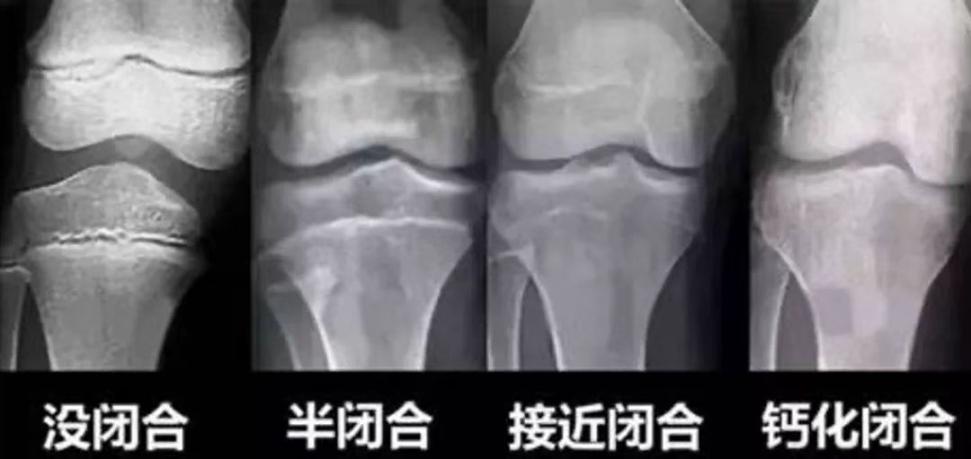

一般情况下,骨龄与骨骺线闭合程度成正比——

● 骨龄偏小,骨骺线闭合时间晚、速度慢,骨骼纵向发展的潜力大;

● 骨龄偏大,骨骺线闭合时间早、速度快,骨骼的生长空间小。